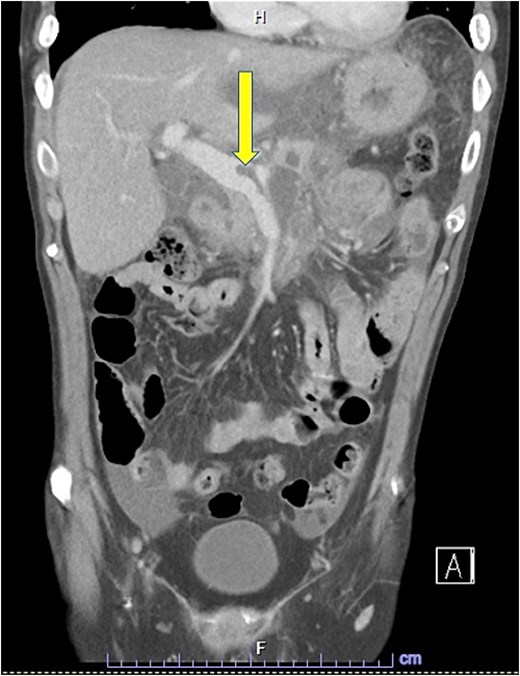

Despite the absence of abdominal symptoms, a computed tomography of the abdomen and pelvis (CTAP) was performed due to markedly elevated lipase levels. The CTAP (Figs 3–5) revealed evidence of acute pancreatitis (Fig. 5, arrow), with a complex peripancreatic fluid collection (Fig. 3, arrow). Additionally, a focal thrombus was observed within the portal venous confluence (Fig. 4, arrow). Further ultrasound of the gallbladder was negative for gallstones (Fig. 6), ruling out gallstone-induced pancreatitis.

CTAP coronal view; complex peripancreatic fluid collection (arrow) with extension behind the splenic vein to lie adjacent to the pancreatic neck and uncinate process.